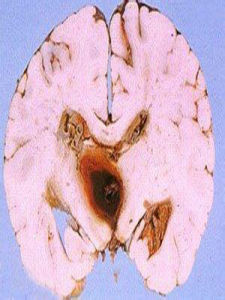

隨著我國人民生活水平的提高及飲食結構改變,高血壓及心血管疾病的發病率呈逐年升高的趨勢,給患者帶來了嚴重的生命隱患,嚴重影響患者心、腦、腎等重要臟器的生理功能,如不及時干預,會導致其功能衰竭,甚至危及生命。腦部血管病變主要表現為腦部血管硬化,腦血管彈性減弱是腦血管硬化初期,一旦出現腦血管硬化,會導致患者腦質量改變、腦血管腔變窄或粗細不均,從而導致腦部血流流速減慢,進而出現腦部供血不足和血栓的形成。

在顱內動脈血管的檢測中,經顱都卜勒超聲檢查較為常用,其檢查操作簡便、無創、重複性好,並且能夠較好的反映血管狹窄及血管畸形等改變。根據分析腦血流信號的改變從而反映動脈彈性和心臟射血、動脈內血液流速與容量變化,了解血管內血流動力學變化情況。經顱都卜勒超聲能夠有效的反映機體腦部血管的彈性情況。